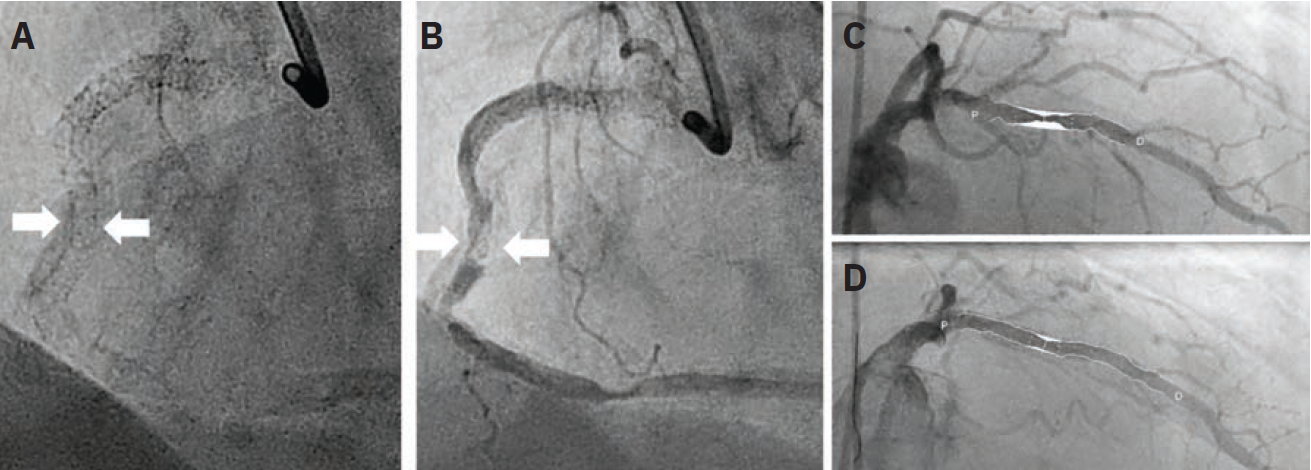

1. Ten Tips and Tricks for Successful Distal True Lumen Wiring From Three-Dimensional Wiring Experts

Wu E, Nagamatsu W, Okamura A

J Invasive Cardiol. 2024 Jun 6. doi:10.25270/jic/24.00096

Abstract: Antegrade wiring is the dominant method used in chronic total occlusion percutaneous coronary intervention (CTO PCI). However, distal cap puncture for distal true lumen wiring remains a significant barrier toward success. Three-dimensional (3D) fluoroscopic wiring can improve the speed, safety, and success of distal cap wiring. In this article, we provide 10 tips for every CTO interventionist to use when performing 3D wiring in distal true lumen wiring.